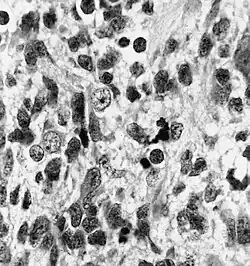

| Histopathology of medulloepithelioma showing characteristic neural tube like strands. | |

Histologically, medulloepithelioma resemble a primitive neural tube and with neuronal, glial and mesenchymal elements.[8][9] Flexner-Wintersteiner rosettes may also be observed.[10]